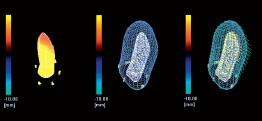

Wall Motion Tracking (WMT) позволяет зафиксировать и проанализировать движение стенок миокарда. WMT отслеживает деформацию миокарда и смещение его участков (спекл-трекинг). Технология может быть использована как в 2D, так и в 3D режимах. Спеклы - это изменения ультразвука отражателями в ультразвуковом пучкеnd ™..Toshiba делает акцент на большой роли стандартизации параметров деформации миокарда и активно поддерживает Объединенную рабочую группу Американского общества эхокардиографии (ASE) и Европейской ассоциации Эхокардиографии (EAE). Анализ WMT может выполняться как в онлайн, так и в автономном режиме на основе файлов DICOM, содержащих необработанные клипы с данными, отправленные на рабочую станцию. WMT незаменим для диагностики ишемических повреждений миокарда и определения точной локализации инфаркта.

Технология 2D Wall Motion Tracking - проводит сегментарный анализ (16 или 17 сегментов по ASE) миокарда для вычисления циркулярной, радиальной и продольной деформации;

Технология 3D Wall Motion Tracking - сердце, объемная трехмерная (3D) структура, а значит и движение сердца и смещение спекл- шумов происходит в трёх плоскостях.

3D-технологии используются для получения полного объема данных о структурном и функциональном состоянии левого желудочка. Чтобы рассчитать движение стенки в трех измерениях, требуется хорошо сбалансированный набор данных с точки зрения пространственного и временного разрешения.